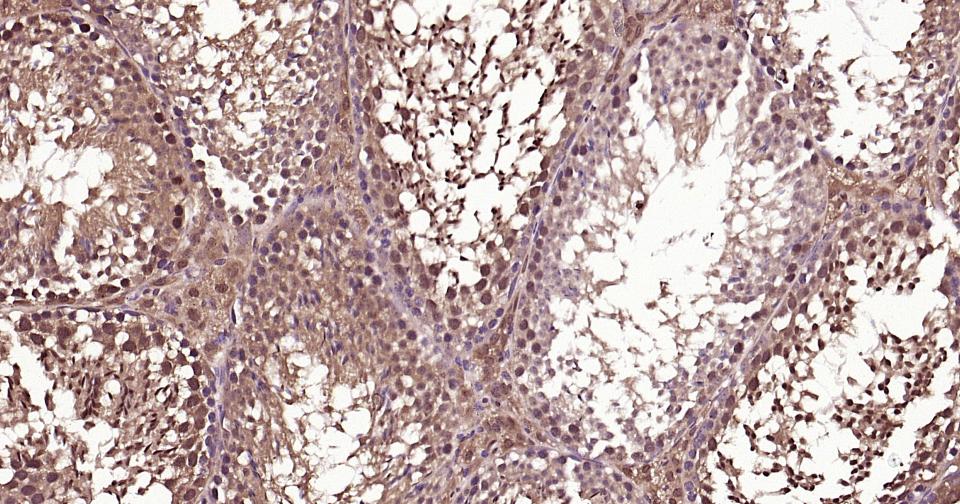

Paraformaldehyde-fixed, paraffin embedded Human Breast Cancer; Antigen retrieval by boiling in sodium citrate buffer (pH6.0) for 15 min; Antibody incubation with K48-linkage specific ubiquitin? Monoclonal Antibody, Unconjugated(bsm-63005R) at 1:200 overnight at 4°C, followed by conjugation to the bs-0295G-HRP and DAB (C-0010) staining and DAB (C-0010) staining.

Paraformaldehyde-fixed, paraffin embedded Human Prostate Tumor; Antigen retrieval by boiling in sodium citrate buffer (pH6.0) for 15 min; Antibody incubation with K48-linkage specific ubiquitin? Monoclonal Antibody, Unconjugated(bsm-63005R) at 1:200 overnight at 4°C, followed by conjugation to the bs-0295G-HRP and DAB (C-0010) staining and DAB (C-0010) staining.